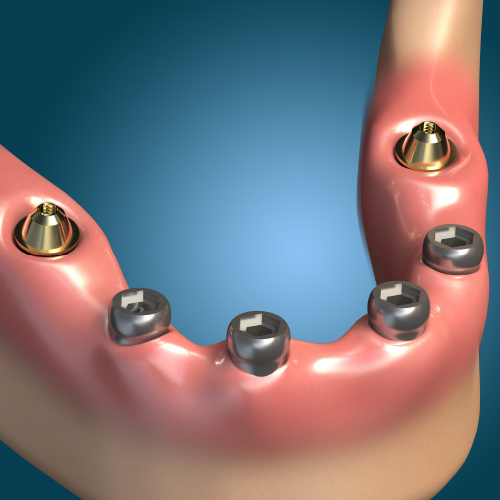

Dental Rehabilitation of the Atrophic Maxilla

Ankur Johri, DDS, MD, FACS

Friday, July 29, 2022

This Compendium eBook features a continuing education (CE) article presents important diagnostic and treatment planning principles of the All-on-4 treatment concept for the rehabilitation of the atrophic maxillary arch, and includes a case report illustrating free-hand implant placement using this treatment approach.

Implantology Solutions

Friday, March 4, 2022

This Compendium eBook offers a continuing education (CE) article that examines treatment planning for full-arch reconstruction with implant overdentures. A long-term case report is also featured in this eBook, highlighting the steps involved in a full-arch reconstruction using transitional ...

Planning Full-Arch Reconstructions for Today and Tomorrow: Implant Overdentures and Fixed Restorations

Michael D. Scherer, DMD, MS

Thursday, September 30, 2021

This Compendium eBook features a continuing education (CE) article that discusses strategic implant treatment planning that takes into consideration the future restoration treatment needs of patients. Download to earn 2 FREE CEU now!

Developments in Implantology

Tuesday, March 9, 2021

This Compendium eBook features a continuing education (CE) article that considers the rationale for graftless alternatives, as well as the data supporting the use of various graftless protocols. In an accompanying clinical materials article, the author addresses modifications in the dental ...

Implant Solutions for the Edentulous Patient

David A. Little, DDS

Saturday, November 21, 2020

This Compendium eBook features a continuing education (CE) article that discusses various implant solutions for the edentulous patient.